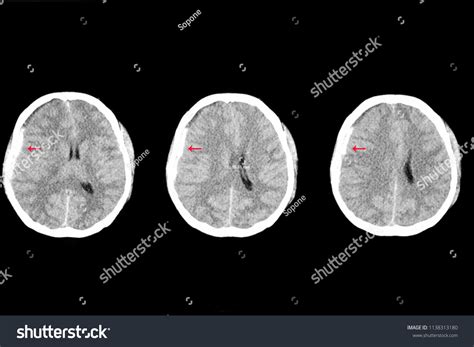

• Imaging tests: Magnetic resonance imaging (MRI) and magnetic resonance venography (MRV) are the most commonly used tests. These can provide detailed images of the brain and venous sinuses, helping to identify blood clots.

• Computed tomography (CT) scan: A CT scan can also be used to detect blood clots, especially in emergency situations.